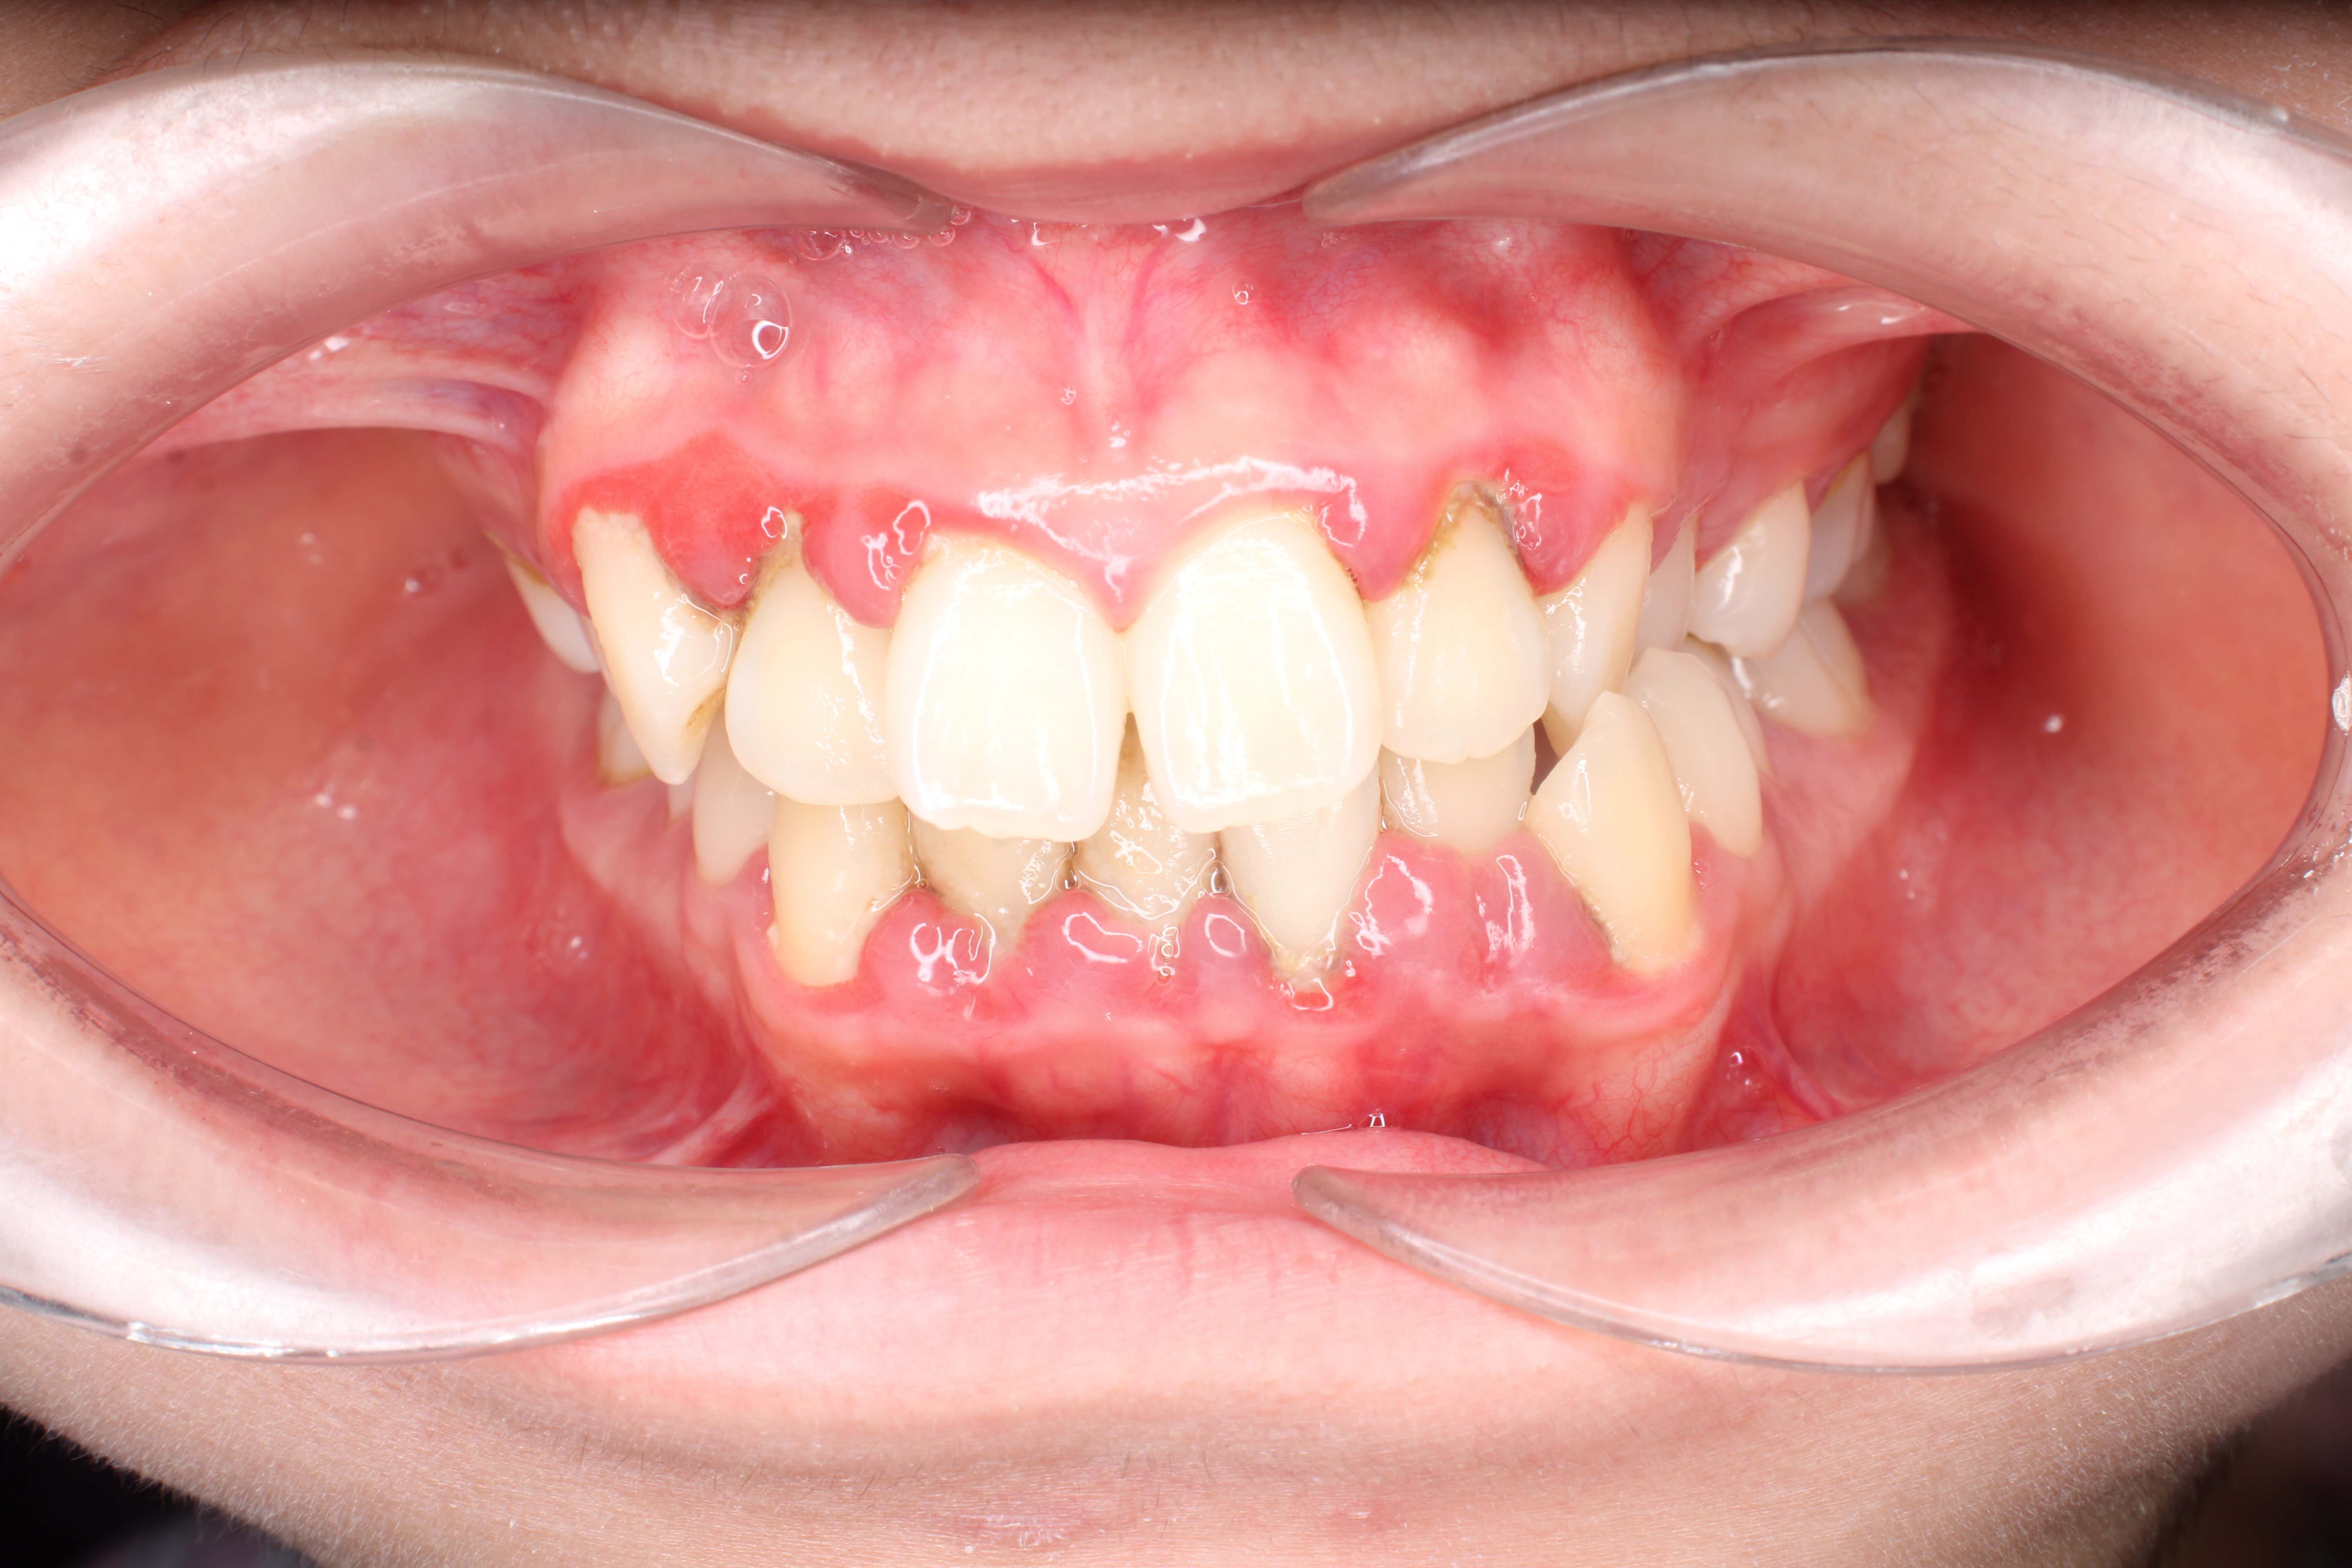

Khách hàng bị viêm lợi, cao răng dưới lợi cũng thuộc nhóm những người không nên niềng răng. Số lượng này chiếm tới 17% trong số các ca cần trì hoãn chỉnh nha.

Cao răng, đặc biệt là cao răng dưới lợi, là nơi trú ngụ của hàng tỷ vi khuẩn gây hại. Khi gắn mắc cài, việc vệ sinh răng miệng trở nên khó khăn, tạo điều kiện cho vi khuẩn tấn công mạnh mẽ vào mô nướu đang nhạy cảm do lực siết răng. Nếu không xử lý dứt điểm, tình trạng viêm sẽ tiến triển thành túi mủ, gây đau đớn và cản trở hoàn toàn tiến độ dịch chuyển răng.

Khách hàng bị viêm lợi rất nặng do không đảm bảo vệ sinh răng miệng

Nếu gặp các tình trạng này, bác sĩ tại Lạc Việt Intech sẽ lấy sạch cao răng và điều trị miễn hó cho khách hàng. Nếu viêm lợi nhẹ, cao răng ít, việc điều trị sẽ đơn giản và nhanh chóng. Nếu nhiều cao răng dưới lợi, viêm nặng thì khách hàng có thể mất vài lần hẹn cùng bác sĩ.